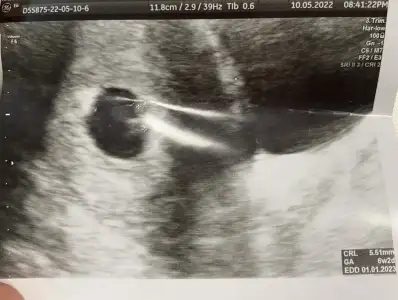

Teşekkür ederim 6+1 karından var hatta atmıştım prenses gibi demiştiniz tekrar atayım :)paşa gibi 7 haftalık görüntüsü var mı?

Karışıklık olmasın diye tekrar atayım, ilk görüntü 6+1 pazar günü olan, 2. Görüntü 6+3 salı günü olan ikisi de karından;bu görüntü 7-8 haftalık civarı mıpazar attığın görüntü peki?

seninki prenses canımKarışıklık olmasın diye tekrar atayım, ilk görüntü 6+1 pazar günü olan, 2. Görüntü 6+3 salı günü olan ikisi de karından;